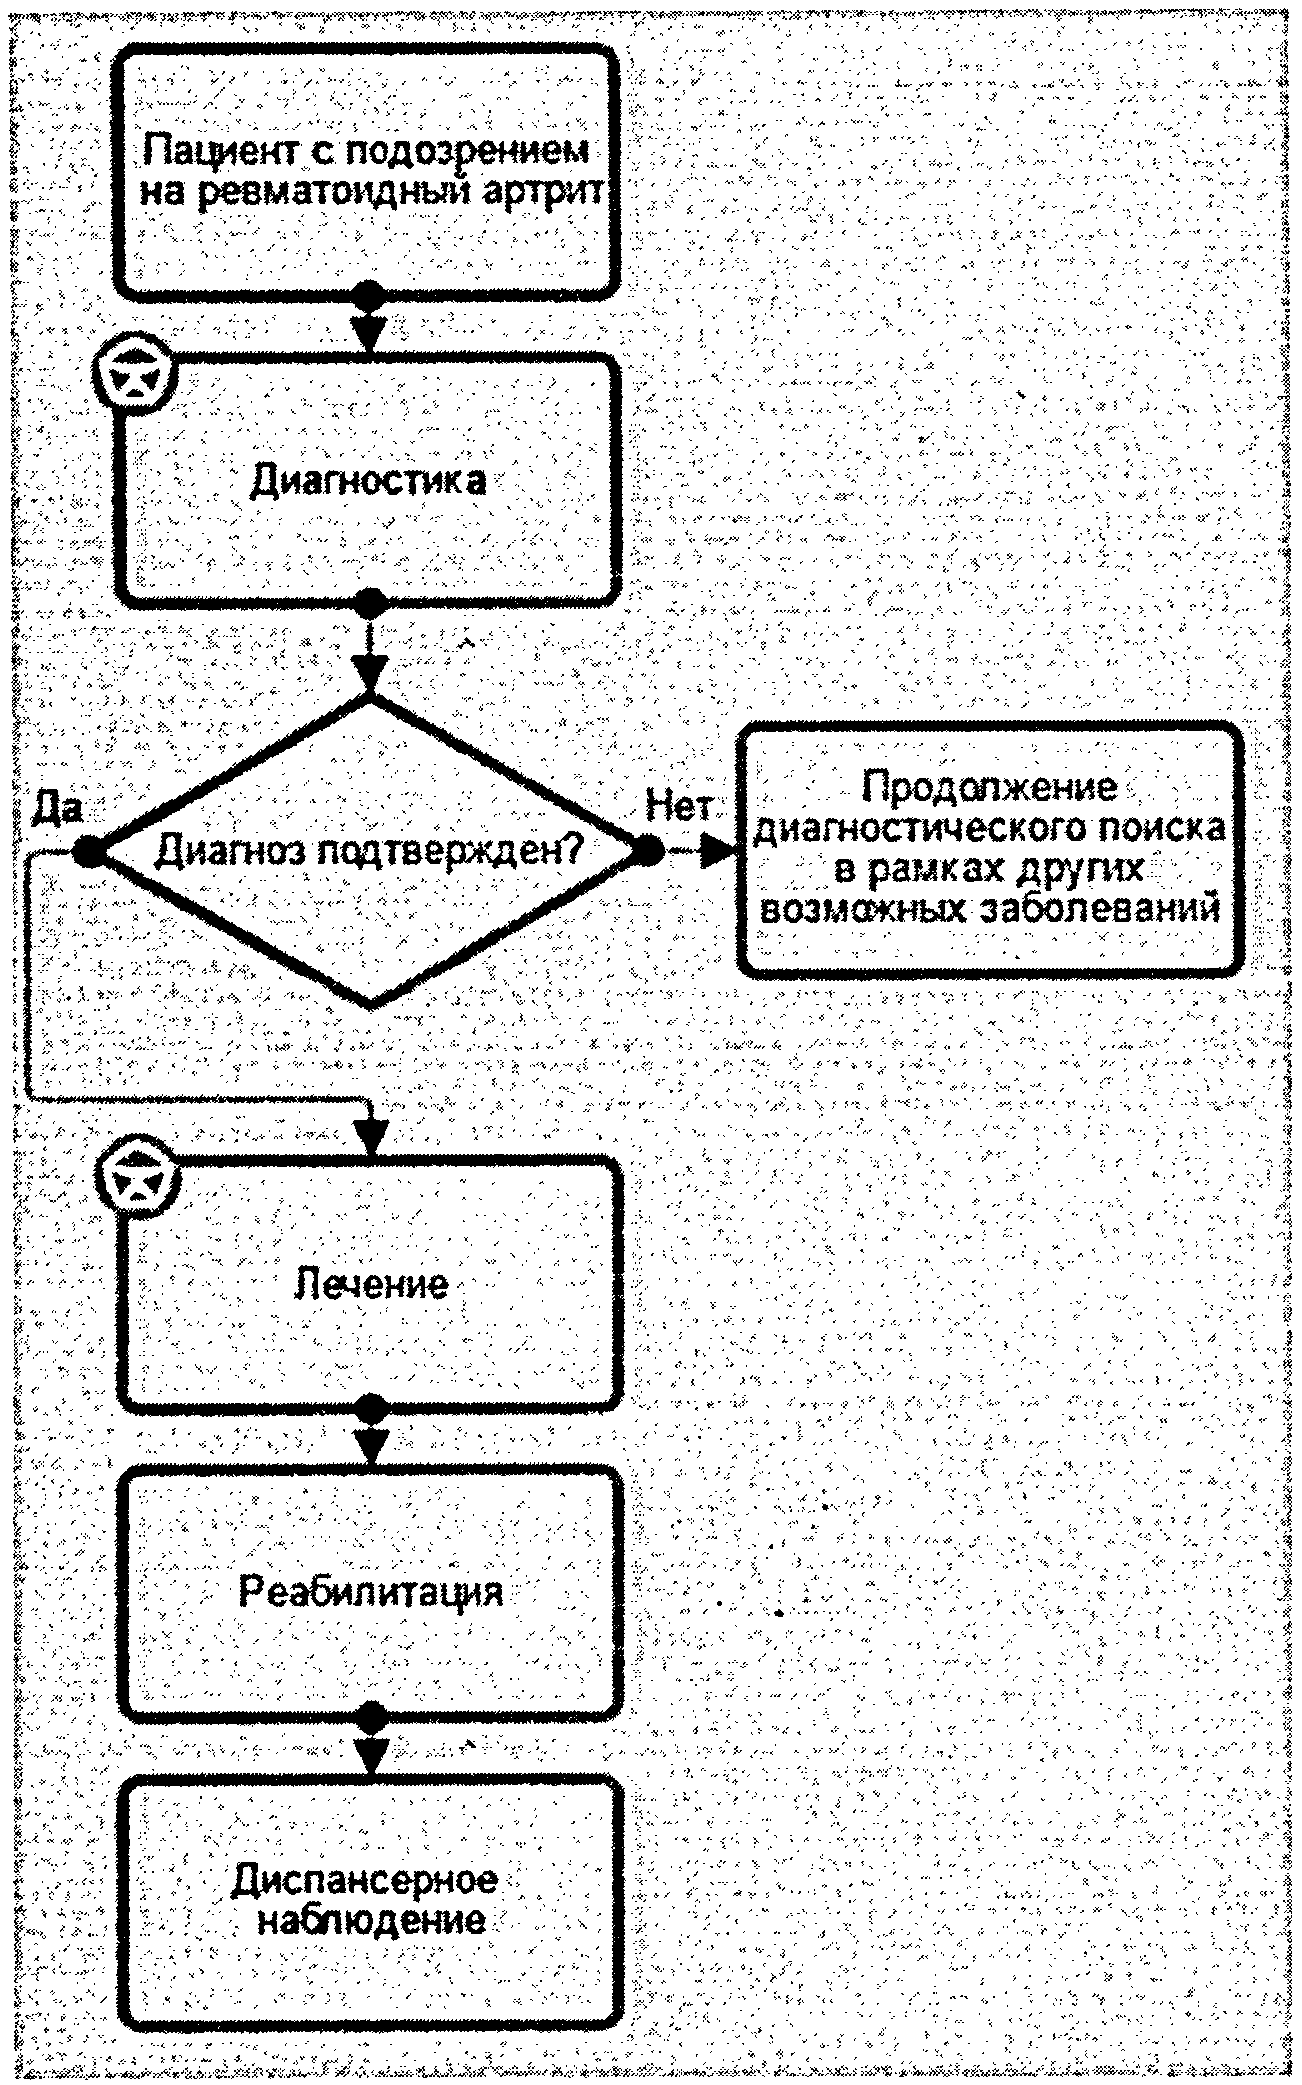

2. Диагностика заболевания или состояния (группы заболеваний или состояний), показания и противопоказания к применению методов диагностики

3. Лечение, включая медикаментозную и немедикаментозную терапии, диетотерапию, обезболивание, медицинские показания и противопоказания к применению методов лечения

- Лечение РА рекомендуется основывать на стратегии "Лечения до достижения цели" ("Treat to target"): активное назначение противовоспалительной терапии, включающей сБПВП, ГИБП, тсБПВП, НПВП, ГК, контроль над состоянием пациента с момента постановки диагноза частый (каждые 3 мес. до достижения ремиссии, каждые 6 мес. после достижения ремиссии) и объективный (с применением количественных методов), изменение схемы лечения при отсутствии приемлемого эффекта терапии [12, 45-55] (приложение Г4, Г5).